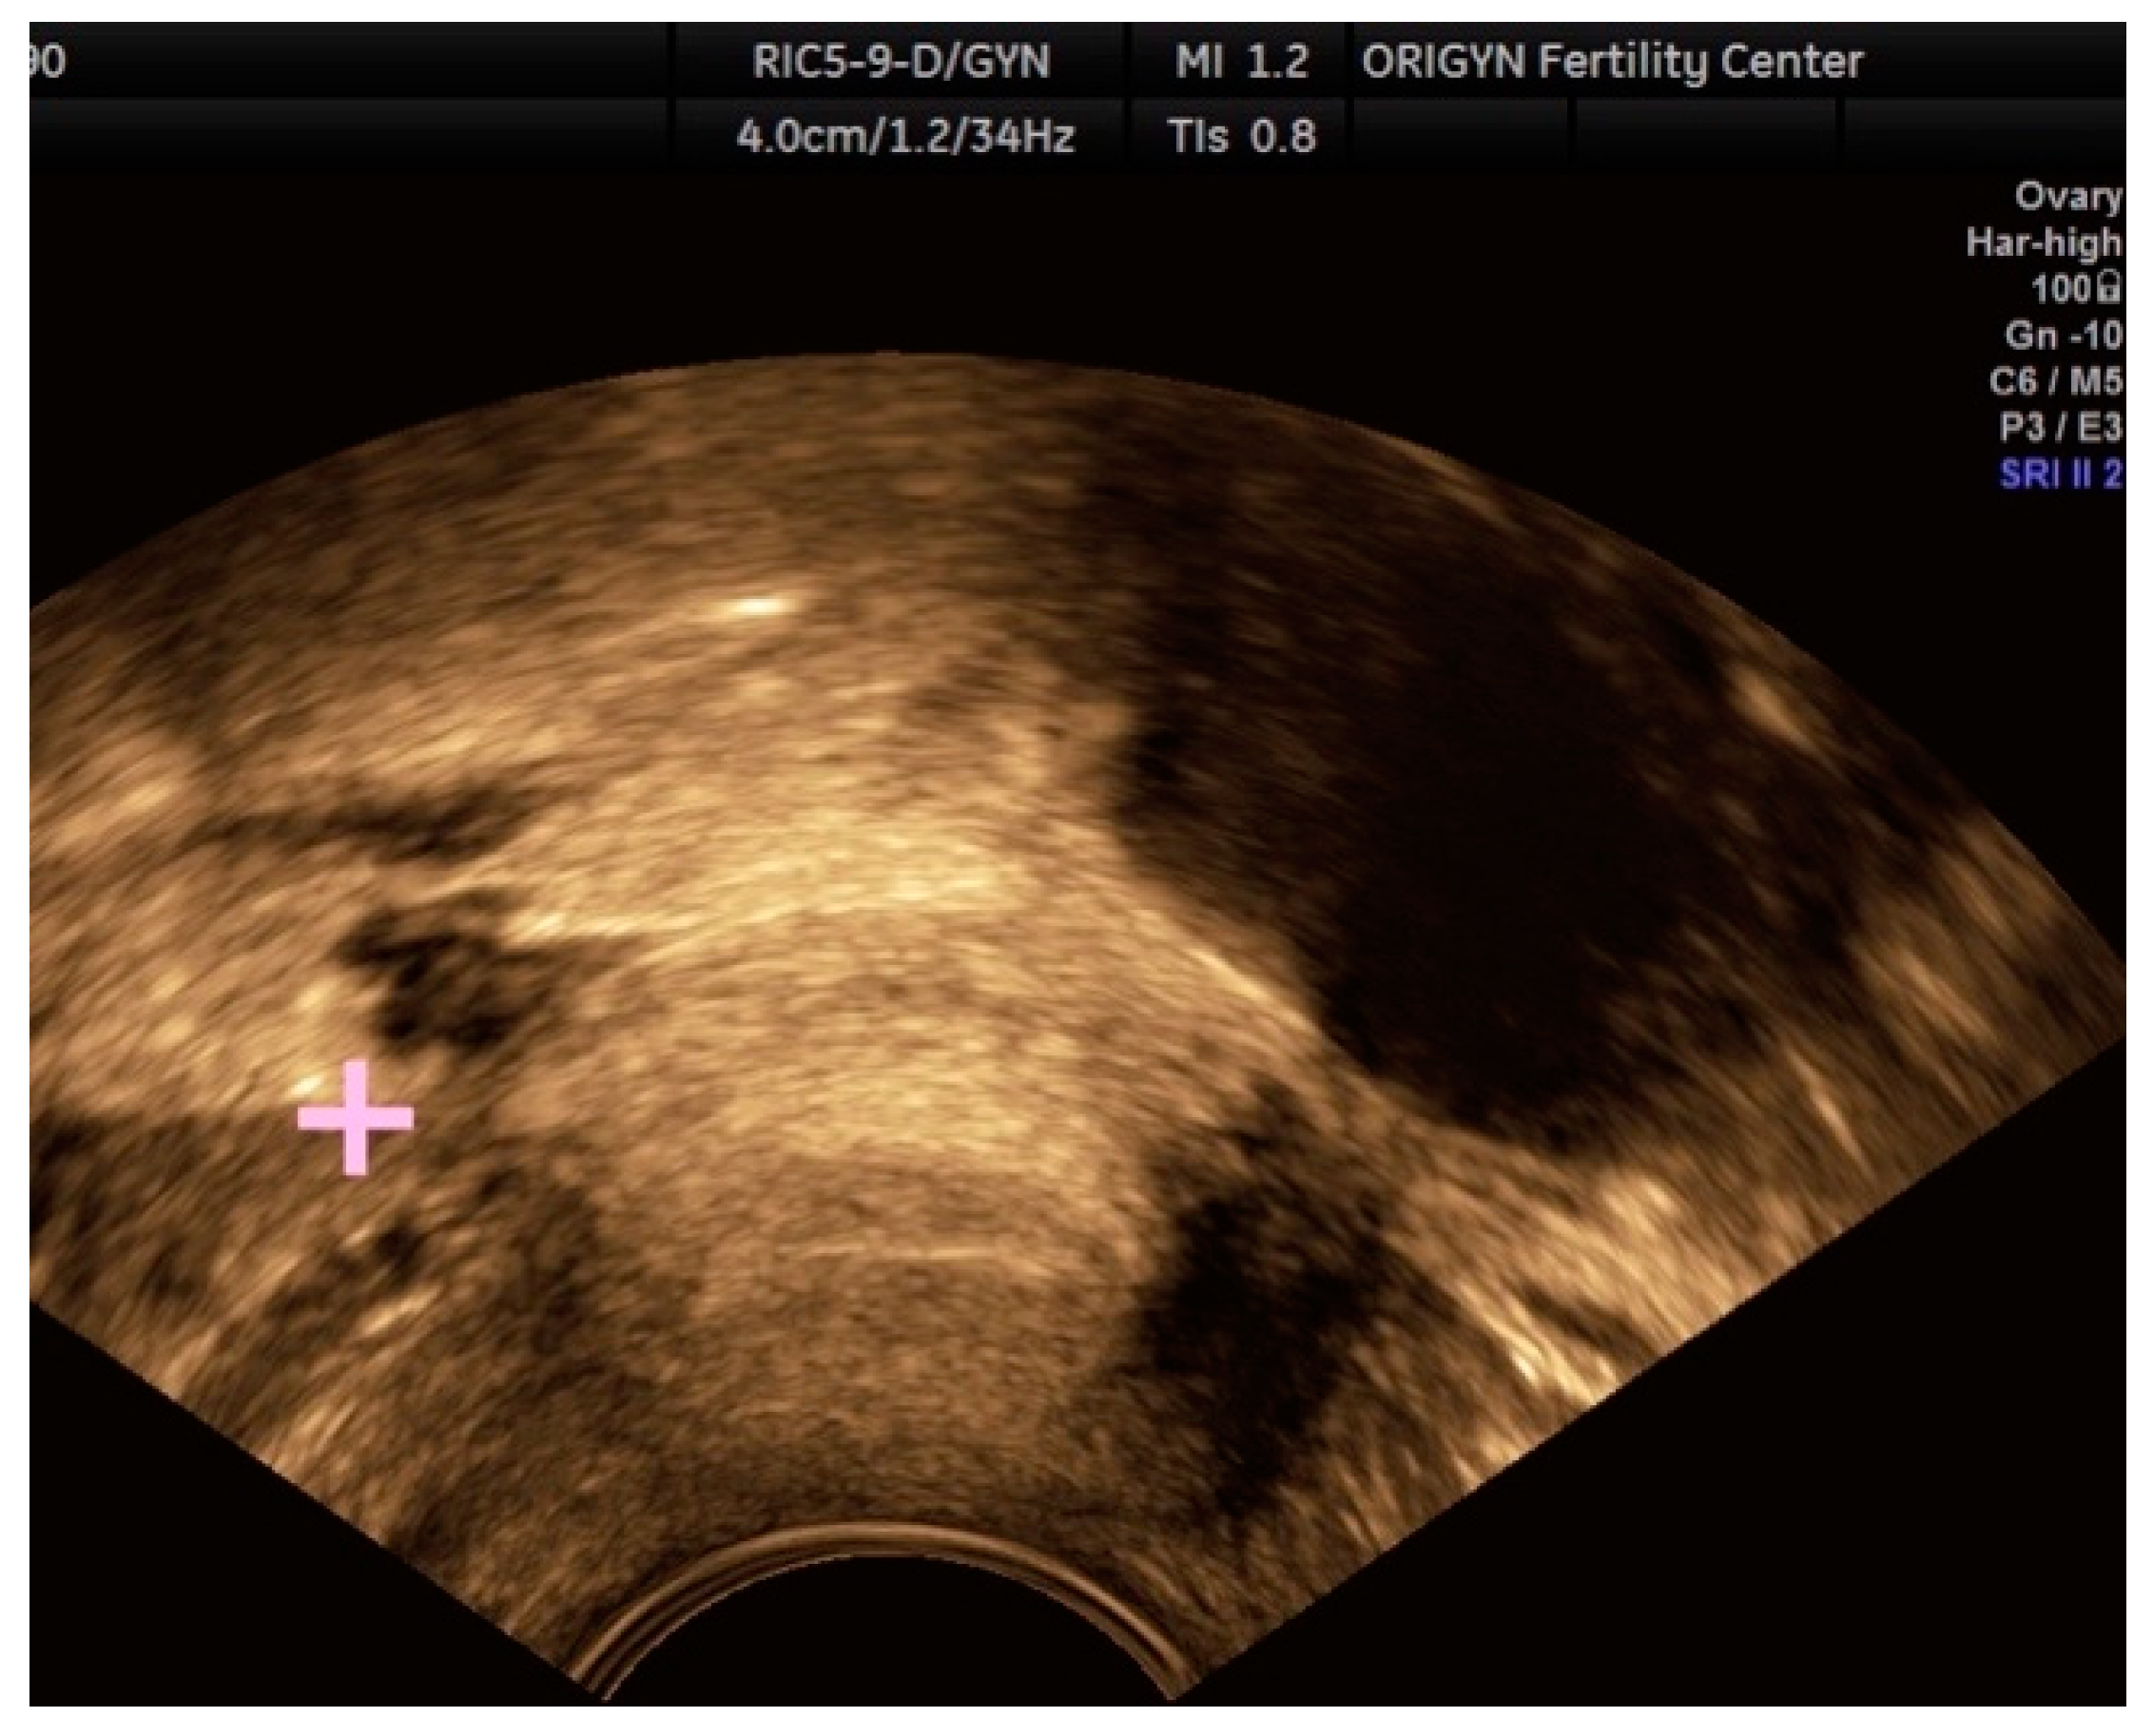

3.1. ADNEXA